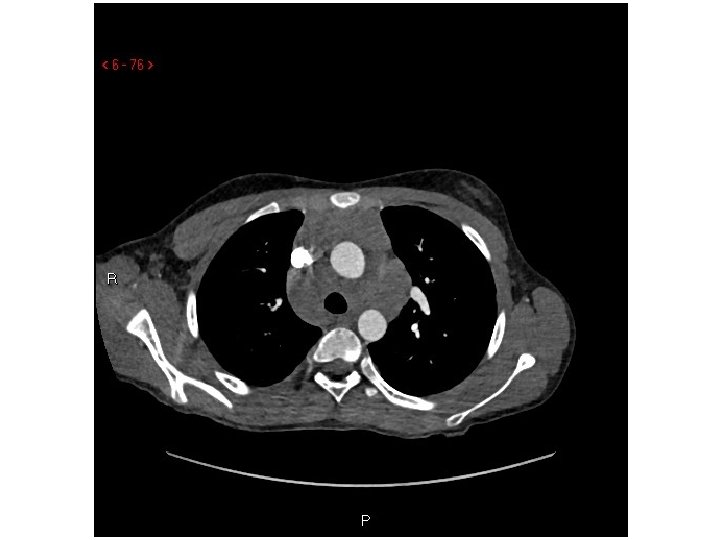

DC, 12 y. o. F • Presented to the ED via EMS with left shoulder, thigh, and rib pain after she rode her bicycle into a concrete wall w/o a helmet • ? LOC, mild HA, no emesis, was moving all extremities after landing in the grass per parents • PMH: seasonal allergies, constipation • PE: significant only for mild abrasions and ecchymosis over left lateral thigh • In ED: FAST, CT head, XR elbow/knee/radius/ulna/shoulder/femur, CXR, CTA chest

Diagnosis/Follow up Diagnosis: Mediastinal& hilar lymphadenopathy/mass Follow up • 1 st clinic visit: Imaging concerning for possible lymphoma, although no worrisome sx, history, labs, or exam findings • PET: “FDG avid mediastinal and hilar lymphadenopathy” • 2 nd clinic visit: fatigue, submandibular adenopathy • CT-guided FNA: “Atypical lymphocytes” – Flow Cytometry: “normal thymic tissue”

Radiographic Features and Ddx: Mediastinal Mass in a Child • Anterior Mediastinum (most common location) – Solid: prominent/ectopic thymus, thymoma, thymic carcinoma, lymphoma, teratoma – Fatty: lipoma, thymolipoma – Cystic: thymic cyst, lymphatic malformation • Middle Mediastinum – Vascular anomalies – Nonvascular lesions: congenital foregut duplication cyst, bronchogenic cyst, esophageal cyst, neurenteric cyst – LAD: primary neoplasm (lymphoma), metastasis, infection • Posterior Mediastinum (usually neurogenic) – Sympathetic ganglion tumors: neuroblastoma, ganglioneuroma – Nerve sheath tumors: schwannoma, neurofibroma, malignant peripheral nerve sheath tumor